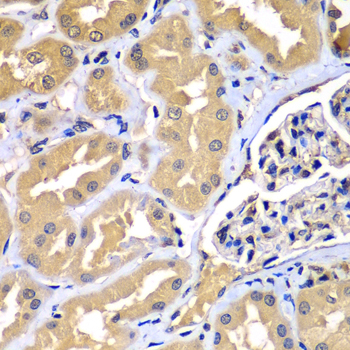

• A7537: image 3

Immunohistochemistry of paraffin-embedded mouse kidney using WIPI2 antibody at dilution of 1:100 (x400 lens).